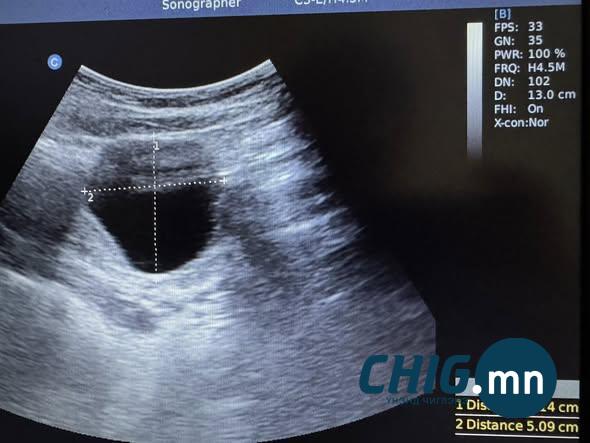

1. Охидын сарын тэмдэг өвдөлттэй ирдэг бол анхаараарай гэсэн рийл үзээд зүгээр л урьдчилан сэргийлээд нэг үзүүлээд үзье гээд үзүүлтэл 5,0 см том уйланхайтай гэхдээ тэр нь одоогоор ямарч өвдөлтгүй 15 настай охин.

| Сэрэмжлүүлэг: 15 настай охин 5 см уйланхайтай, ээж хүү хоёр элэгний ижил өөхлөлттэй байна |